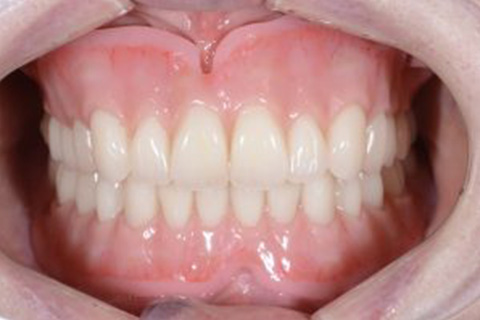

症例2

歯がグラグラで噛めない。骨が少なくてインプラントできない。という主訴でご来院頂いた患者様に対して「特殊プラスティック義歯」を使用した入れ歯の症例

術前

入れ歯での治療後